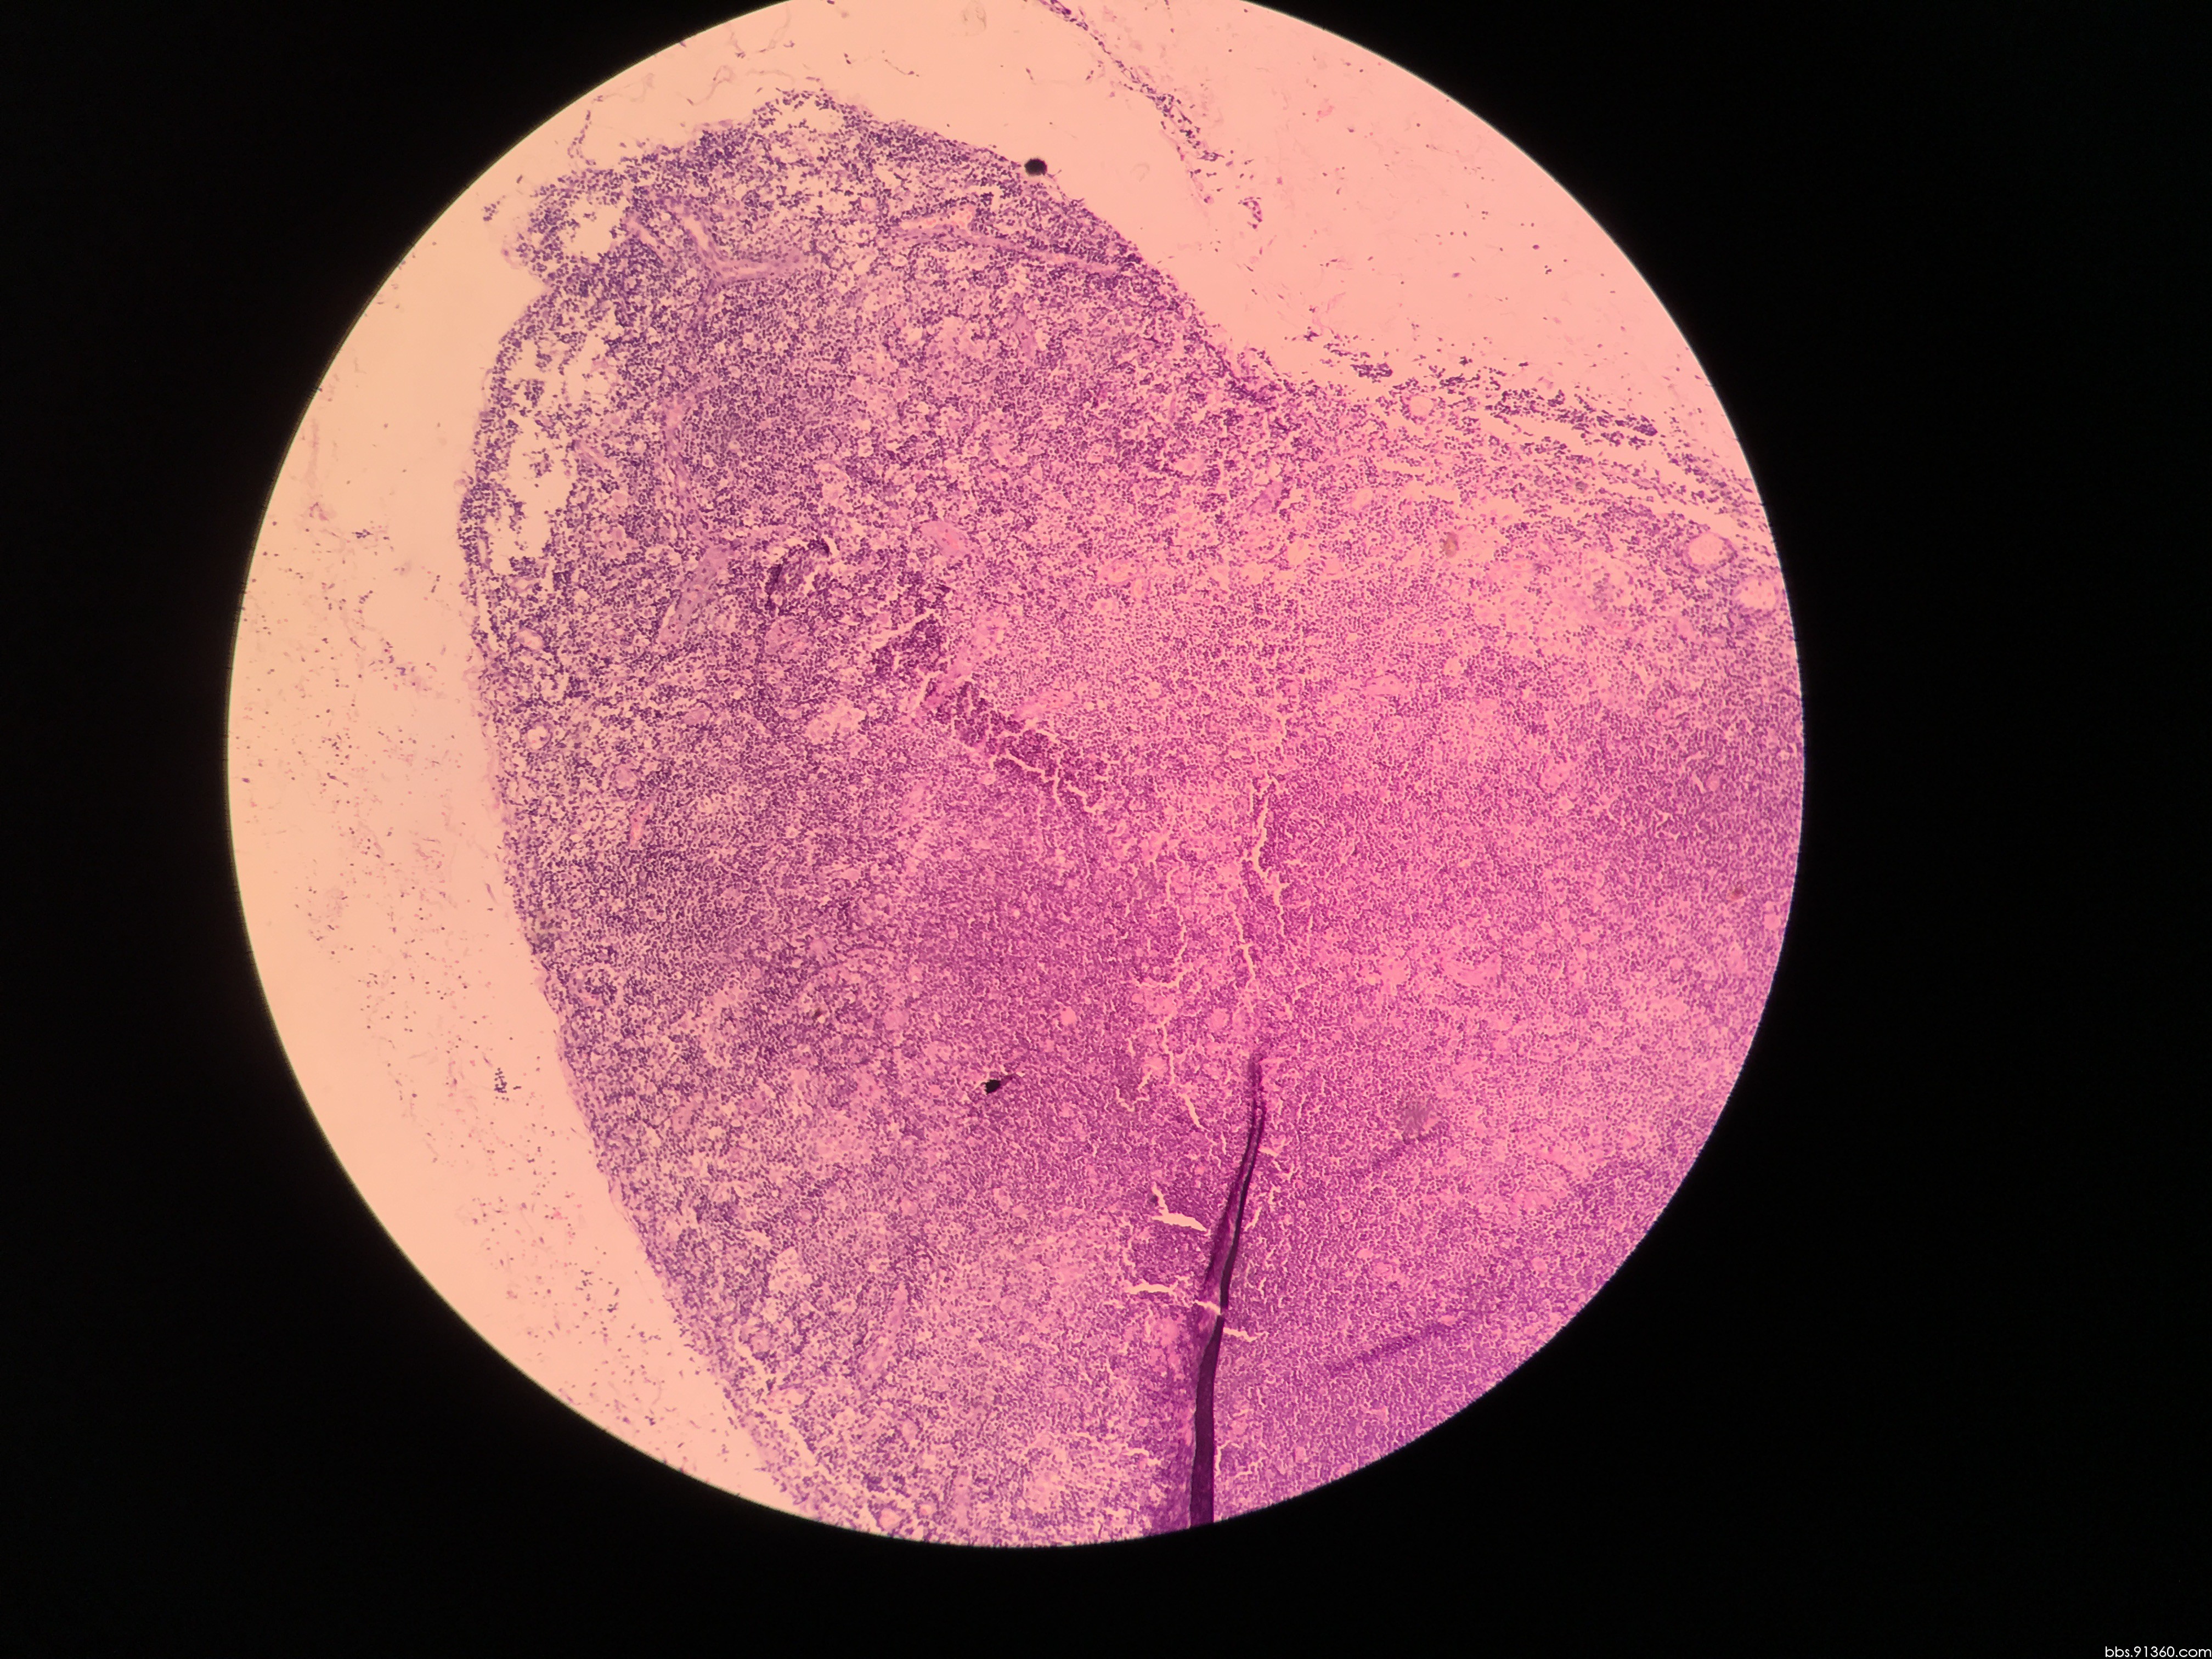

球结膜肿物病例2016.8.1【91360皮肤沙龙病例64】

图片尺寸800x600